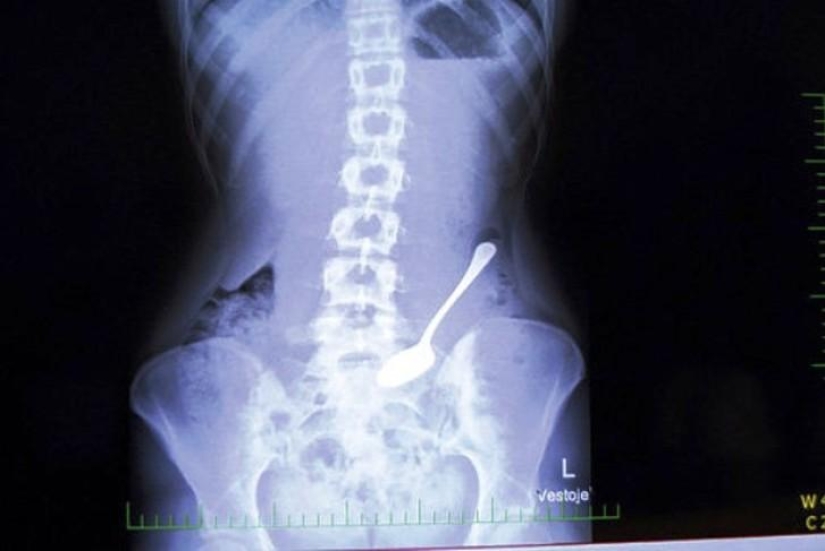

1. Spoon.